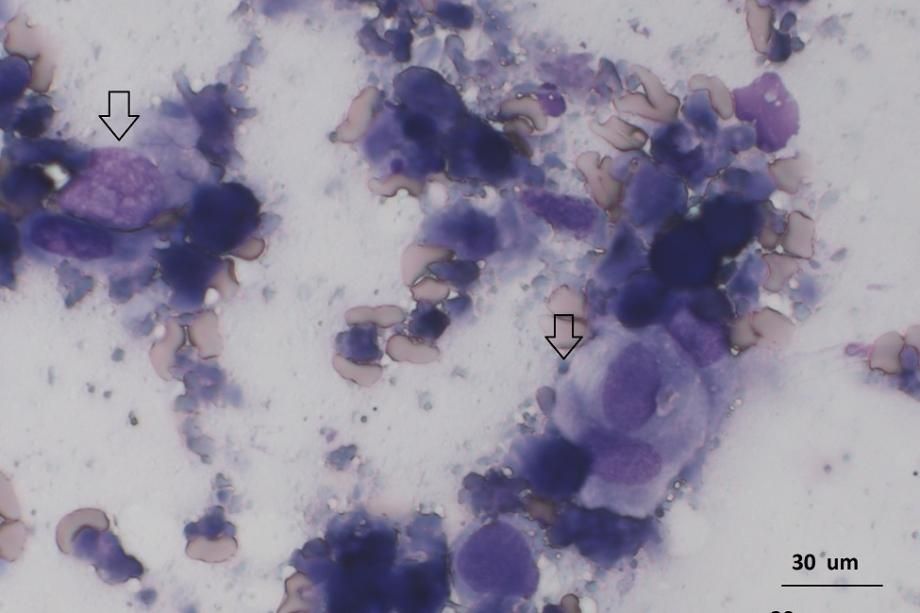

In einem externen Labor werden die Proben zelltechnisch und bakteriologisch untersucht: In der Prostataprobe wird eine eitrige Entzündung mit Bakterienbeteiligung gefunden (obere Aufnahme); die bakteriologische Kultur liefert denn auch einen entsprechenden bakteriellen Erreger. Krebszellen werden keine gefunden. Beim Lymphknoten wird jedoch leider nicht wie erhofft nur eine Aktivierung durch den eitrigen Infekt in der Prostata festgestellt, sondern es werden Tumorzellen gefunden: Die lichtmikroskopische und weiterführende immunzytochemische Untersuchung zeigt, dass der Lymphknoten mit Karzinomzellen (ein bösartiger Drüsen- und Oberflächengewebskrebs) durchsetzt ist (untere Aufnahme). Es ist davon auszugehen, dass die Prostata neben dem eitrigen Infekt auch eine Krebserkrankung aufweist und der Lymphknoten von Tochtergeschwulsten (Metastasen) besetzt worden ist.